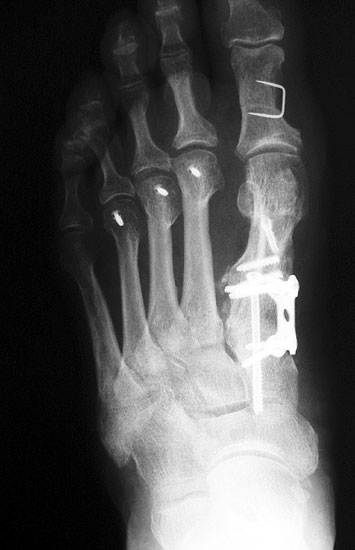

Die dorsoplantaren Röntgenaufnahmen zeigen eine Open-wedge Technik mit der normalerweise ein erhöhter intermetatarsaler Winkel gut zu korrigieren ist (Abbildung 3). Die Wirksamkeit einer Basisosteotomie ist umso größer, je proximaler diese durchgeführt wird. Je weiter distal die Osteotomie, umso geringer die Korrektur. Auf den postoperativen Bildern ist der distal unverändert große Abstand zwischen Metatarsale I und Metatarsale II erkennbar, bei gleichzeitiger Subluxation des Großzehengrundgelenks und dezentrierten Sesambeinen. Darüber hinaus finden sich initiale degenerative Veränderungen im Großzehengrundgelenk. Klinisch bestand eine hohe Weichteilspannung, bei verkürzter Extensor- und Flexor hallucis longus Sehne.  Daher wurde ein verkürzendes Verfahren zur Revision gewählt (Abbildung 4). Die Lapidusarthrodese stellt ein sehr zuverlässiges Verfahren zur Behandlung von Hallux valgus Rezidiven dar 9. Die Fusion des Tarsometatarsale-I-Gelenks kombiniert Stabilität mit einem hohen Korrekturpotenzial. Aufgrund der verfahrensimmanenten Verkürzung des ersten Strahls und der in diesem Fall bereits präoperativ vorhandenen Transfermetatarsalgie wurde die Entscheidung für eine verkürzte Weil-Osteotomie am zweiten bis fünften Strahl gefällt. Die Kombination beider Verfahren führte zu einem homogenen Metatarsale-Index und zu einer gleichmäßigen plantaren Druckverteilung 10. Die Hallux valgus interphalangeus Fehlstellung wurde mit einer Akin-Osteotomie korrigiert.